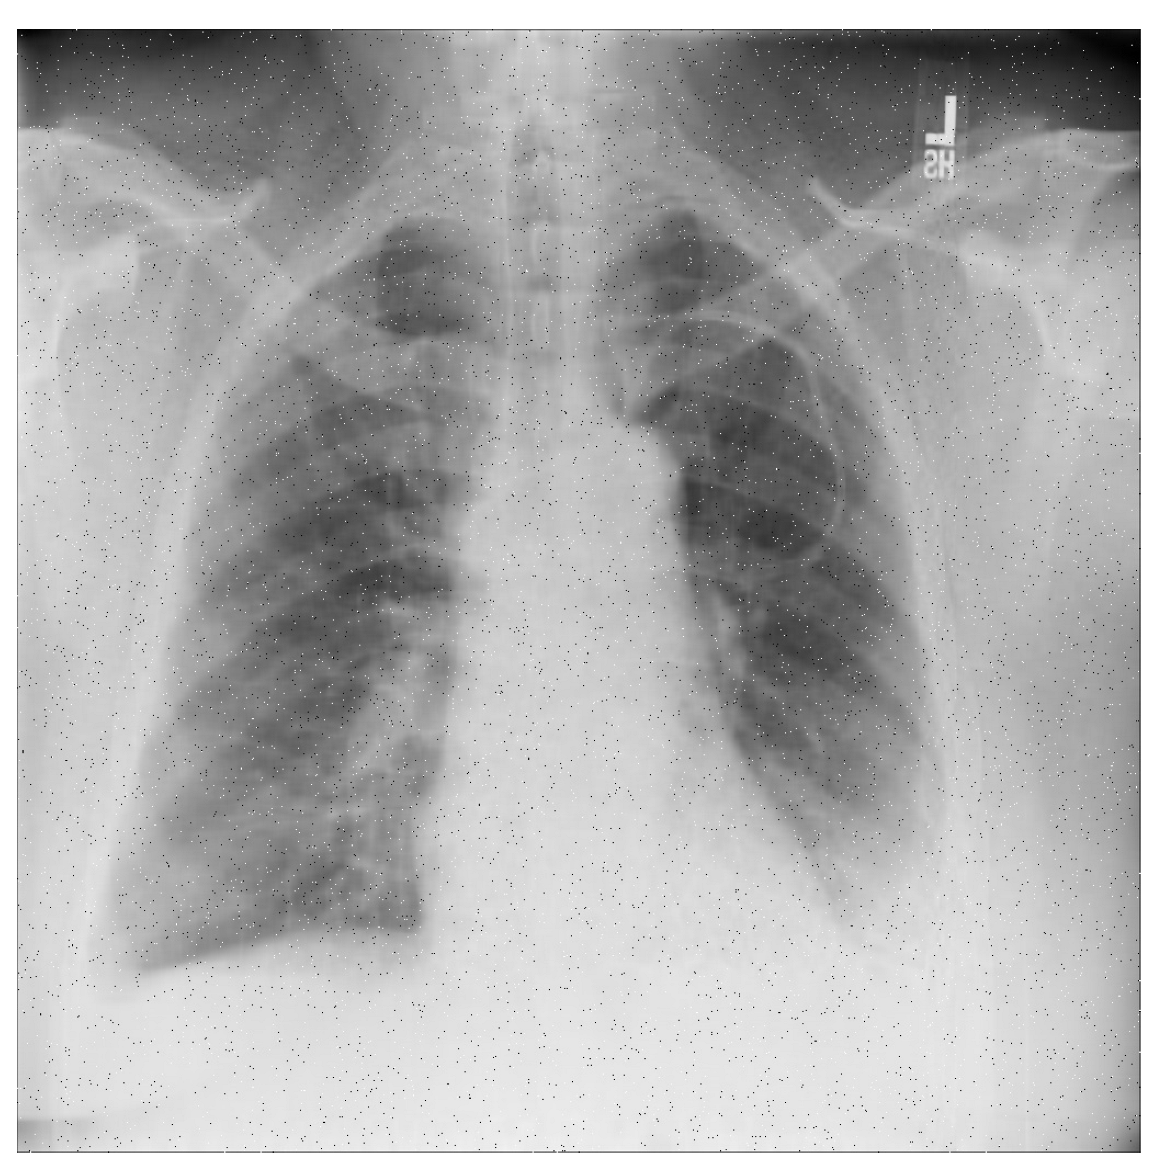

Figure 14 shows an example of typical chest X-ray images used for diagnosis. It can be observed that there are ground-glass opacities in the lungs of certain patients, which are identified using green rectangles. Pulmonary lobes and patchy consolidations are identified using blue ovals, indicating the presence of fibrosis or nodules. Doctors often use these features to determine whether patients are in a state of pneumonia, as well as its severity. Our model is designed to learn these features in order to achieve correct classification.

Figure 14. Analysis and diagnosis using patient CXR images.

Applsci 13 00454 g014